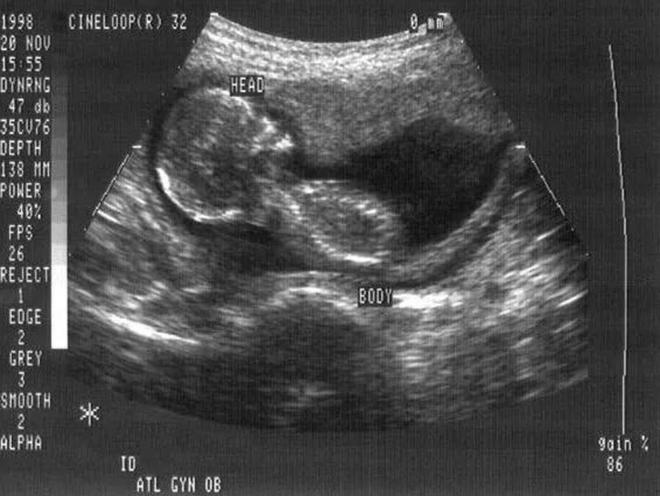

▲ 孕妇怀孕期间的B超图像